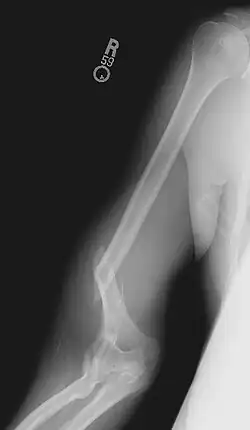

Blessures

Un bras de fer exerce un couple et une torsion importante sur l'os de la partie supérieure du bras, l'humérus, à un niveau rarement atteint dans d'autres activités physiques[14]. Les os de la plupart des humains ne sont pas habitués à de telles contraintes, et des blessures peuvent survenir très facilement. Le trait de fracture passe généralement au niveau d'une ligne située à mi-chemin entre l'épaule et le coude, ou un peu en dessous.

La tendance naturelle d'un pratiquant de bras de fer inexpérimenté est de pousser la main, le poignet et l'épaule dans la même direction de façon coordonnée, contre la force appliquée par l'adversaire. Toutefois, en tournant l'épaule de cette façon, on ne fait qu'ajouter de la pression à la torsion déjà appliquée à l'humérus par l'adversaire. US Arm Sports prévient du danger de « laisser votre épaule en avant de votre main ». Il est préférable de pivoter l'épaule et le bras, afin de ne jamais laisser la main en arrière de l'épaule.